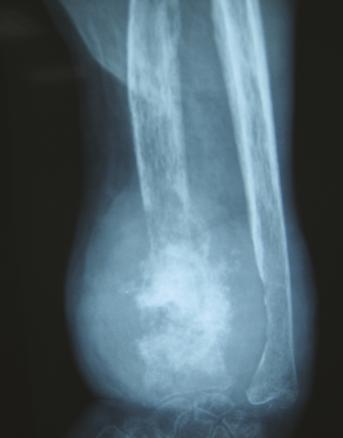

Elle est admise à l’hôpital deux ans plus tard pour des douleurs mixtes et une tuméfaction douloureuse du tiers distal de l’avant-bras gauche, dure et fixe (fig. 1 ). À l’examen physique, la patiente est grabataire et souffre de douleurs osseuses provoquées diffuses, avec une sarcopénie. La radiographie standard met en évidence une importante ostéolyse radiale inférieure, avec rupture des corticales, associée à des images d’ossifications en regard s’étendant aux parties molles épaissies (fig. 2 ). Le même aspect est confirmé sur l’IRM (fig. 3 ). La tomodensitométrie (TDM) thoraco-abdomino-pelvienne est normale. La mammographie ne retrouve pas d’anomalie. La biopsie chirurgicale montre une lésion inhabituelle associant une substance amorphe, une ostéogenèse et des cellules atypiques. Un diagnostic formel n’a pas pu être posé et il n’y avait pas d’arguments pour une origine maligne ou une tumeur osseuse primitive sur le prélèvement. Par ailleurs, le bilan de fractures multiples n’a pas mis en évidence de syndrome inflammatoire biologique. En revanche, une hypophosphorémie a motivé la réalisation d’une scintigraphie osseuse montrant un aspect évocateur d’ostéomalacie.

Elle est admise à l’hôpital deux ans plus tard pour des douleurs mixtes et une tuméfaction douloureuse du tiers distal de l’avant-bras gauche, dure et fixe (